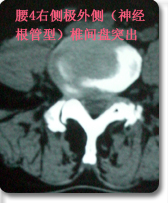

后路内窥镜下(XTube)经单侧神经孔腰椎体间融合,椎弓根螺钉复位内固定术(TLIF)

采用后路内窥镜下(XTube)经单侧神经孔腰椎体间融合,椎弓根螺钉复位内固定术,以治疗极外侧腰椎间盘突出(神经孔型)伴腰椎不稳。 优点:通过单侧经神经孔入路途径达到椎间隙,从而达到椎间减压和植骨融合目的。该手术途径单侧入路,显露清楚,不需过度牵拉神经。为外科医生提供了一个能显著减少PLIF手术的很多风险和限制的融合方式。本手术将内窥镜(XTube)与TILIF手术的优点集于一身达到更小的创伤更好的手术效果。